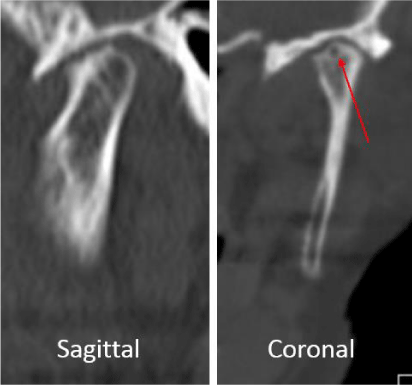

A 53-year-old male presented with a complicated musculoskeletal history consisting of head and neck dystonia and suprahyoid musculature spasms resulting in painful recurrent mandibular subluxation. Examination revealed a mouth-opening of 60 mm with ongoing subluxation due to muscle spasms. The CT scan of the left side suggested severe degenerative changes with multiple rounded erosive foci and a hazy periosteal reaction at the skull base (Figure 6). The T1 weighted MRI showed low signal intensity in the condylar bone marrow on the left. The disc was not visualized and there was no evidence of intra-articular mass (Figure 7). Diagnostic arthroscopy of the left showed a large central perforation of the disc with remarkable nodular synovitis. Synovial biopsy, synovectomy and debridement were performed (Figure 8). Histologic examination showed PVNS (Figure 9). Additional surgical treatment for the dislocation and the degenerative changes of the TMJ was deferred until further control of the muscular dystonia was achieved.

A 72-year-old female presented with left-sided jaw pain. Examination revealed tenderness over the left masseter, a mouth-opening of 35 mm and bilateral joint noises. Her left side had direct and indirect loading. The CT scan showed degenerative changes of the left condyle with a 2x2 mm subchondral cyst (Figure 10). The MRI revealed a degenerative left condyle with a deformed disc. The T2 weighted imaging showed a superior joint space effusion (Figure 11). Diagnostic arthroscopy showed retrodiscal synovitis, chondromalacia and a perforated disc. There were crystal-like structures within the synovium antero-medially. Synovial biopsy, debridement and partial synovectomy were performed (Figure 12). Histologic examination showed proliferative synovitis with calcium pyrophosphate deposition (Figure 13). The patient was referred for rheumatological management of CPPD but no treatment was initiated due to symptom resolution. On her 6-month follow-up her pain had resolved; she was maintaining a regular diet and her mouth-opening had become 45 mm with no joint loading.